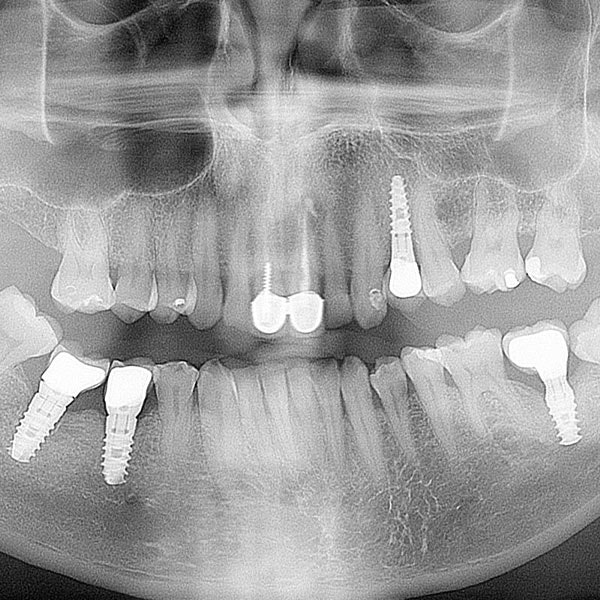

We know some patients forgo dental treatment because they've had uncomfortable experiences in the past, but our office goes to great lengths to provide gentle and effective treatment. Our technology helps patients maintain their oral health and function by allowing us to monitor oral health with X-rays, place dental implants in the best possible locations, and create dental crowns that are indistinguishable from natural teeth. Whether you need a simple checkup or new dentures, we can provide comfortable, satisfying care.